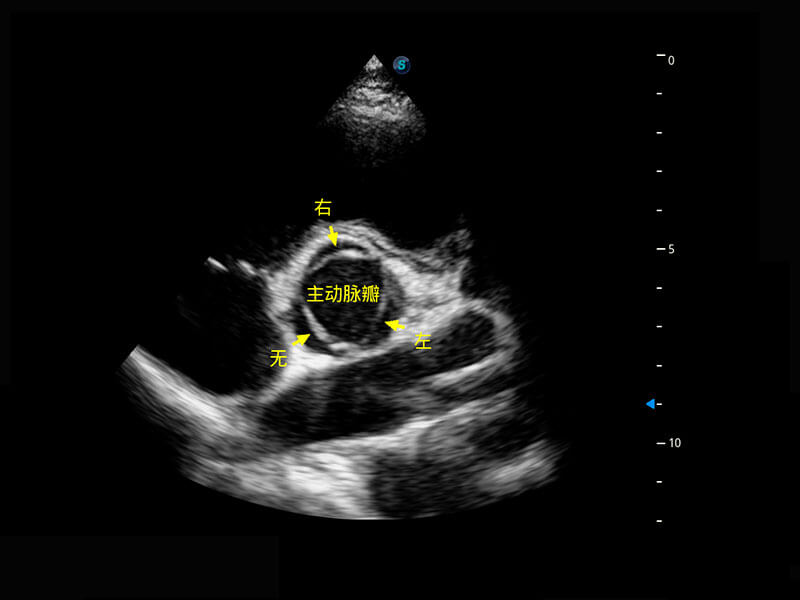

• 新生儿肝血管癌

• 新生儿心脏